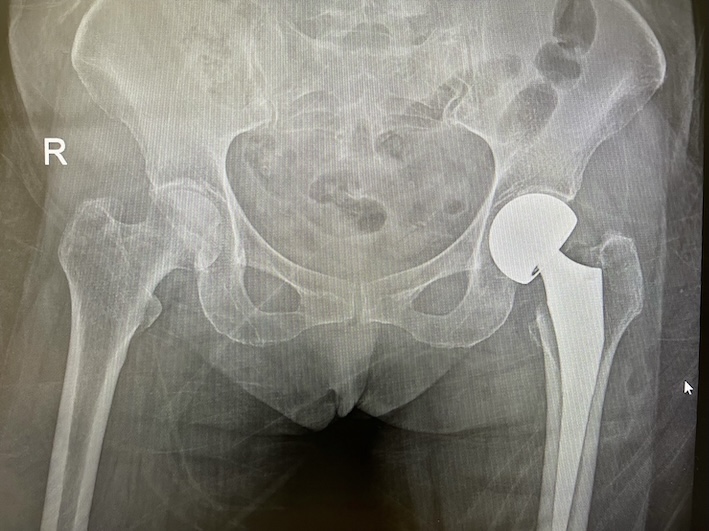

รูปกระดูกสะโพกก่อนผ่าตัด

รูปกระดูกสะโพกหลังผ่าตัด

รอยหักบริเวณสะโพกส่วนใหญ่จะเกิดที่บริเวณคอสะโพก ( Femoral neck fracture) หรือต่ำลงมาบริเวณ แนวรอยต่อระหว่างคอสะโพกและกระดูกต้นขา ( Intertrochanteric fracture)

การผ่าตัดเพื่อรักษาภาวะกระดูกสะโพกหัก อาจเป็นการผ่าตัด ดามกระดูกด้วยโลหะ หรือการผ่าตัดเปลี่ยนข้อสะโพกเทียม ร่วมกับการทำกายภาพบำบัดหลังผ่าตัด จะช่วยให้ผู้ป่วย สามารถกลับมาลุกยืน เดินได้ และช่วยหลีกเลี่ยงข้อแทรกซ้อนที่ เกิดจากการต้องนอนนาน ไม่สามารถลุกได้ ต้องเป็นผู้ป่วยติดเตียง เช่น แผลกดทับ การติดเชื้อทางเดินหายใจ ภาวะลิ่มเลือดอุดตันในขา ซึ่งอาจทำให้ผู้ป่วยเสียชีวิตได้